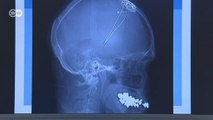

Crean el primer aparato que monitoriza los síntomas del Parkinson

Marca-passo cerebral inibe sintomas do Parkinson